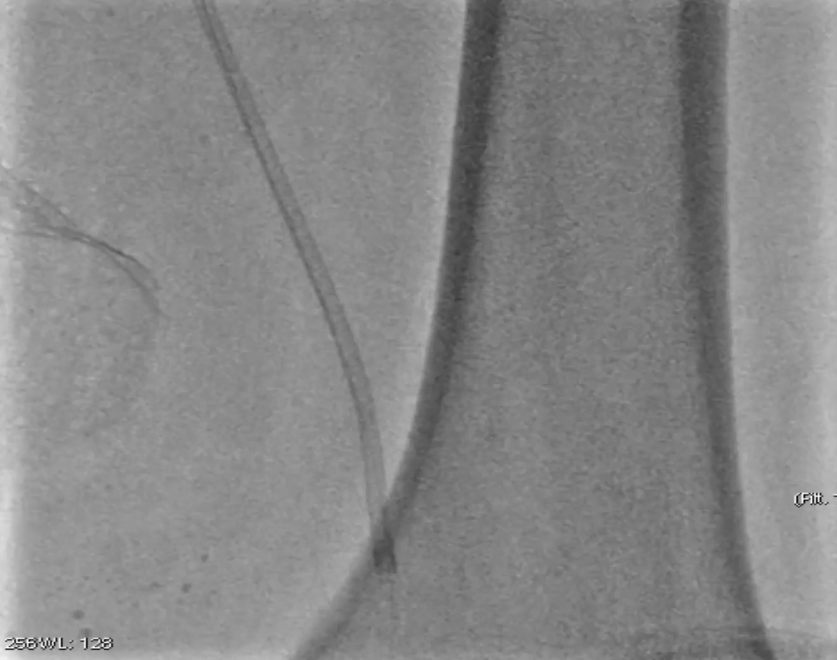

预扩张:先用3mm球囊对病变段预扩张,便于后续器械导入。

保护伞置入:于腘动脉P2段水平放入6mm Spider 保护伞,预防栓塞。

定向旋切:采用新一代Hawk-Plus定向斑块旋切装置进行减容。对于支架内闭塞段,放大图像,确保刀头在可视范围内,反复旋切至接近支架边缘;

对于支架远端病变段,分别采用4个方向各旋切1次,完成初期减容。

器械优势:刀头弧度更大,与血管壁接触面积广,切除效率更高;